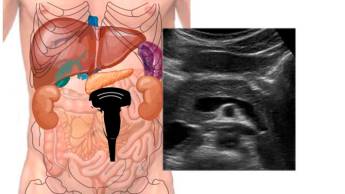

Орган расположен глубоко в ретроперитонеальном пространстве, позади желудка и брюшины, что ограничивает возможности физического осмотра. Ультразвуковое исследование служит базовым методом первичной диагностики, позволяя оценивать размеры и структуру железы, выявлять признаки воспалительных изменений и определять особенности главного панкреатического протока.

Во время ультразвукового исследования анализируются размеры поджелудочной железы, четкость ее контуров, эхогенность паренхимы, состояние главного панкреатического протока и особенности желчевыводящих путей, которые могут влиять на работу органа. Часто УЗИ поджелудочной железы проводят в комплексе с обследованием печени и желчного пузыря.

УЗИ поджелудочной железы занимает 15–30 минут. Пациент располагается на спине или на левом боку — в зависимости от того, какие отделы органа требуют детальной визуализации.

На кожу живота наносится гель, обеспечивающий плотный контакт датчика. Врач перемещает датчик по передней брюшной стенке в продольных, поперечных и косых проекциях. Для улучшения визуализации может потребоваться изменение пациентом положения тела или выполнение короткой задержки дыхания во время процедуры.